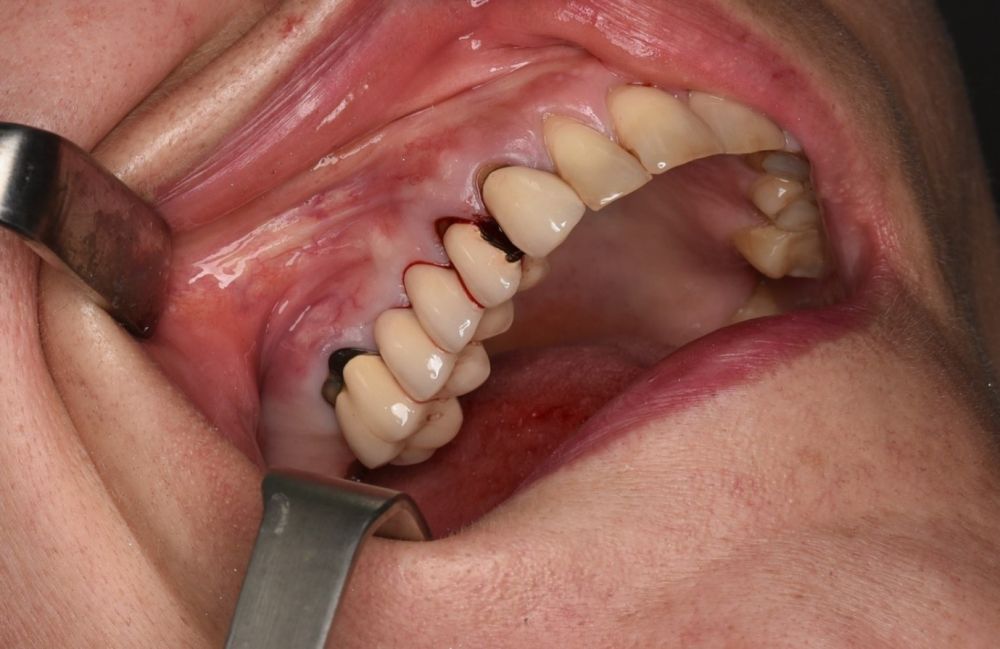

En la historia clínica, no se evidenciaron antecedentes médico-quirúrgicos de interés, alergias medicamentosas conocidas, ni hábitos tóxicos y no presentaba tratamiento médico habitual. Se observó a la exploración intraoral la movilidad de la prótesis fija y caries bajo las coronas con afectación radicular de los pilares 1.4 y 1.7 (Figura 1).

El abordaje quirúrgico del seno se realizó mediante un colgajo a espesor total trapezoidal con una incisión supracretal con descargas verticales vestibulares mesial a 1.3 y distal a 1.7 (Figura 5).